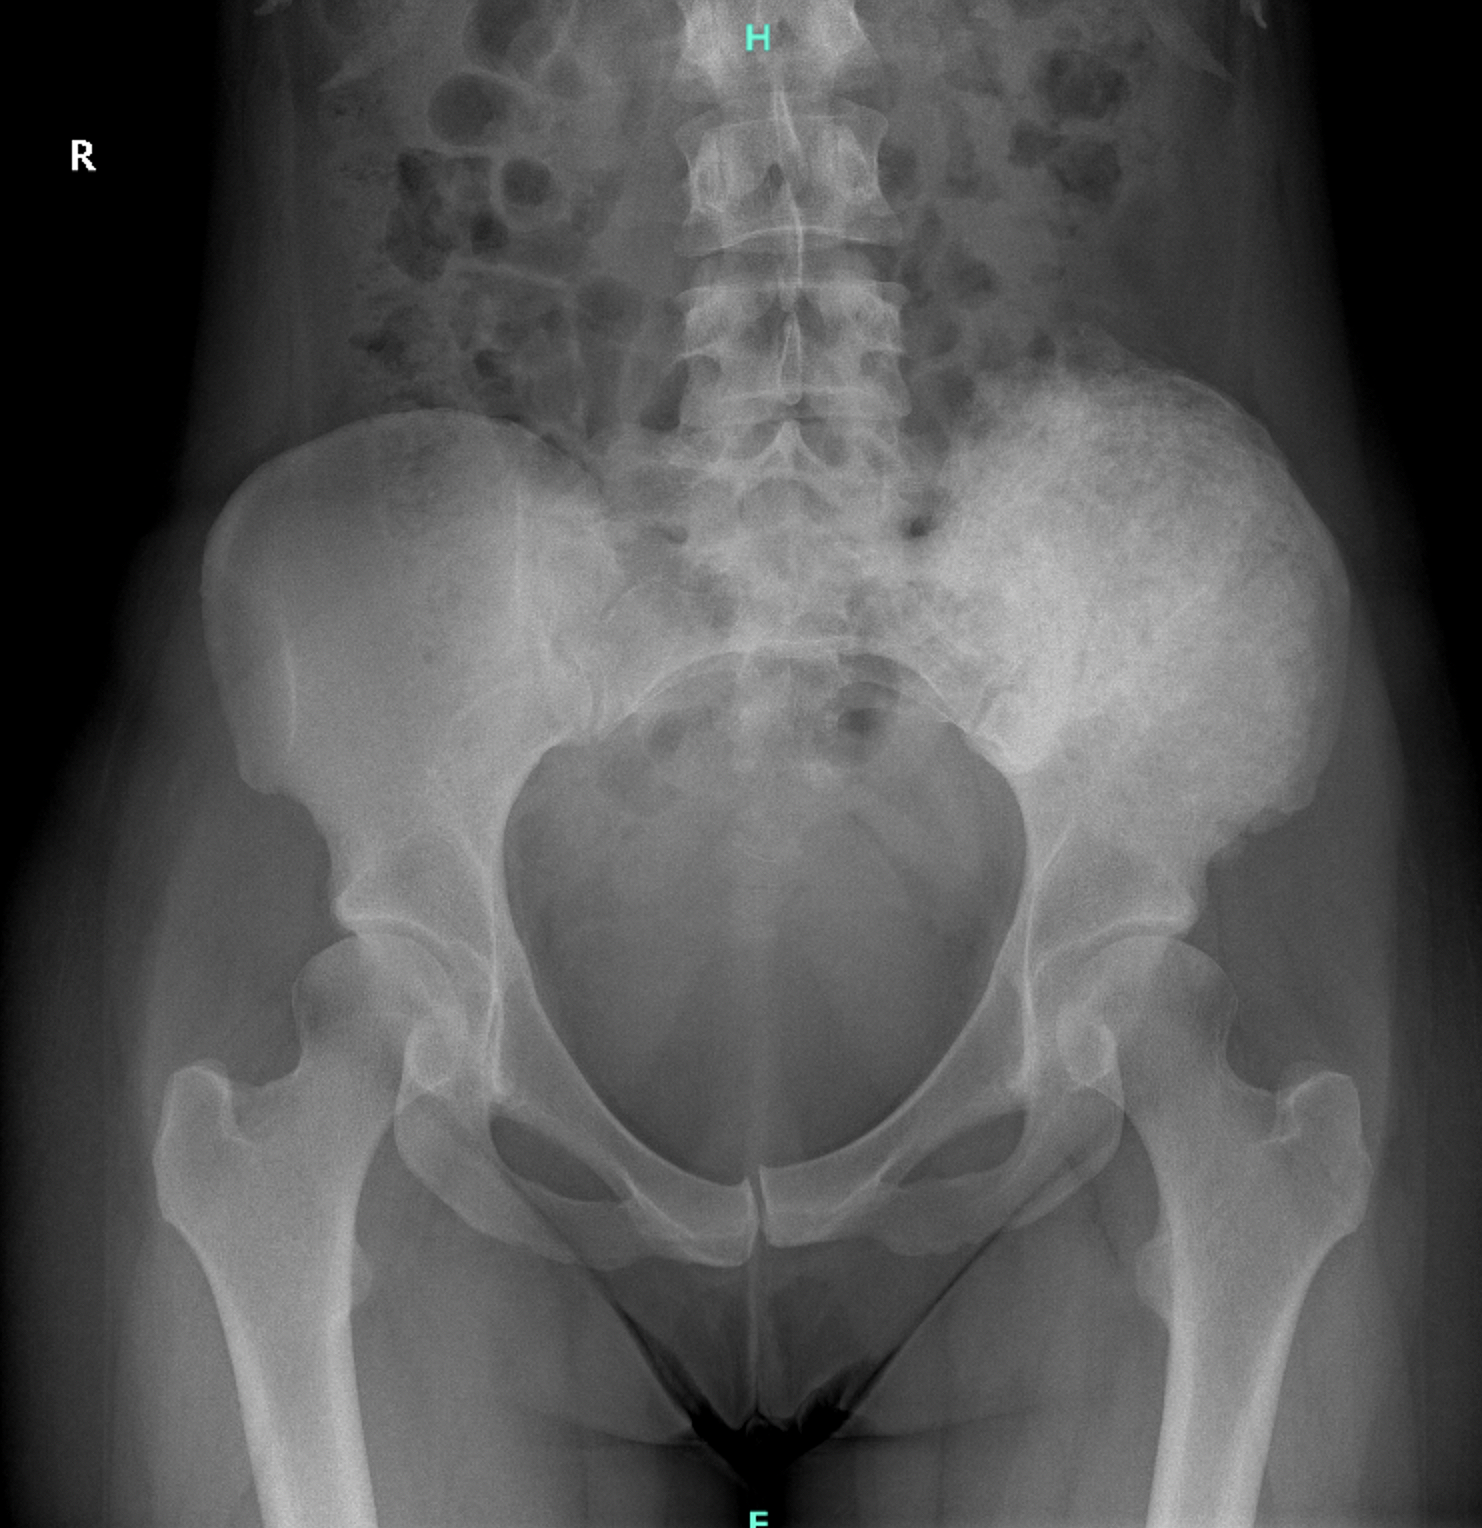

A 27-year-old female patient presented with a giant cell tumor of the left iliac wing that extended into the sacrum. After one year of neoadjuvant DENOSUMAB therapy,

surgical removal was indicated. Since the acetabulum was tumor-free, the hip joint could be preserved. The surgical objective was to achieve wide resection margins

Figure 1: Preoperative pelvic X-ray showing a giant cell tumor in the left iliac wing